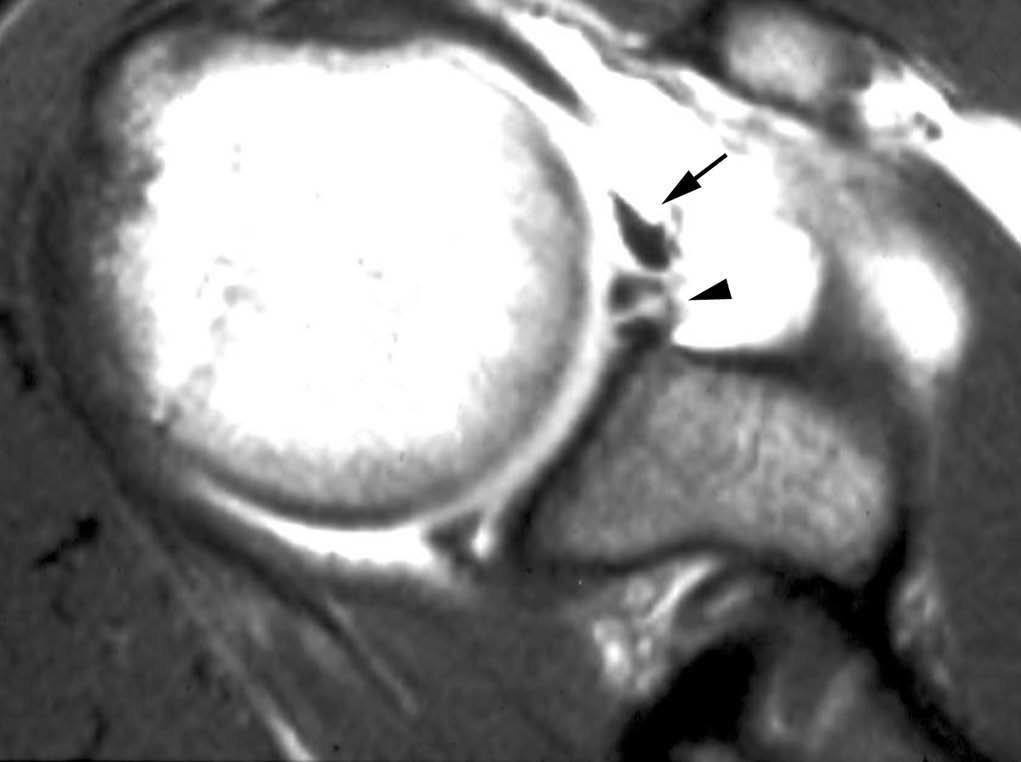

Lesión de Bankart

La lesión de Bankart se produce durante una dislocación anterior e inferior de la cabeza humeral, con impactación de la misma contra el borde anteroinferior de la glenoides, causando un arrancamiento del LG con rotura capsuloperióstica. Al mismo tiempo, se produce frecuentemente una fractura por impactación de la cabeza humeral (lesión de Hill Sachs) (fig. 9). En ocasiones, dicha lesión se acompaña de una fractura del borde anterior e inferior de la glenoides (Bankart óseo).

Fig. 9.--Lesión de Bankard y Hill-Sachs. Artrorresonancia axial T1, donde se observa un desprendimiento completo del labio glenoideo (flecha larga en A) con una rotura capsuloperióstica (cabezas de flecha en A). Nótese la fractura por compresión del margen posterosuperior de la cabeza humeral, representando una lesión de Hill-Sachs (flechas en B).